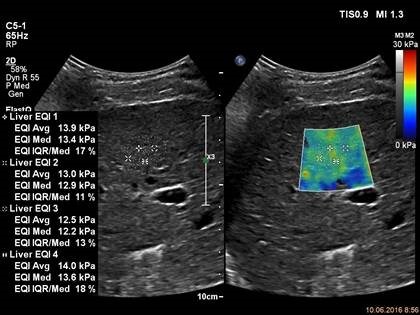

Для исследования используется прибор EPIQ 7, датчик С5-1, приложение ElastQ Проведенные измерения показывают высокую степень жесткости, характерную для цирроза ее ткани.